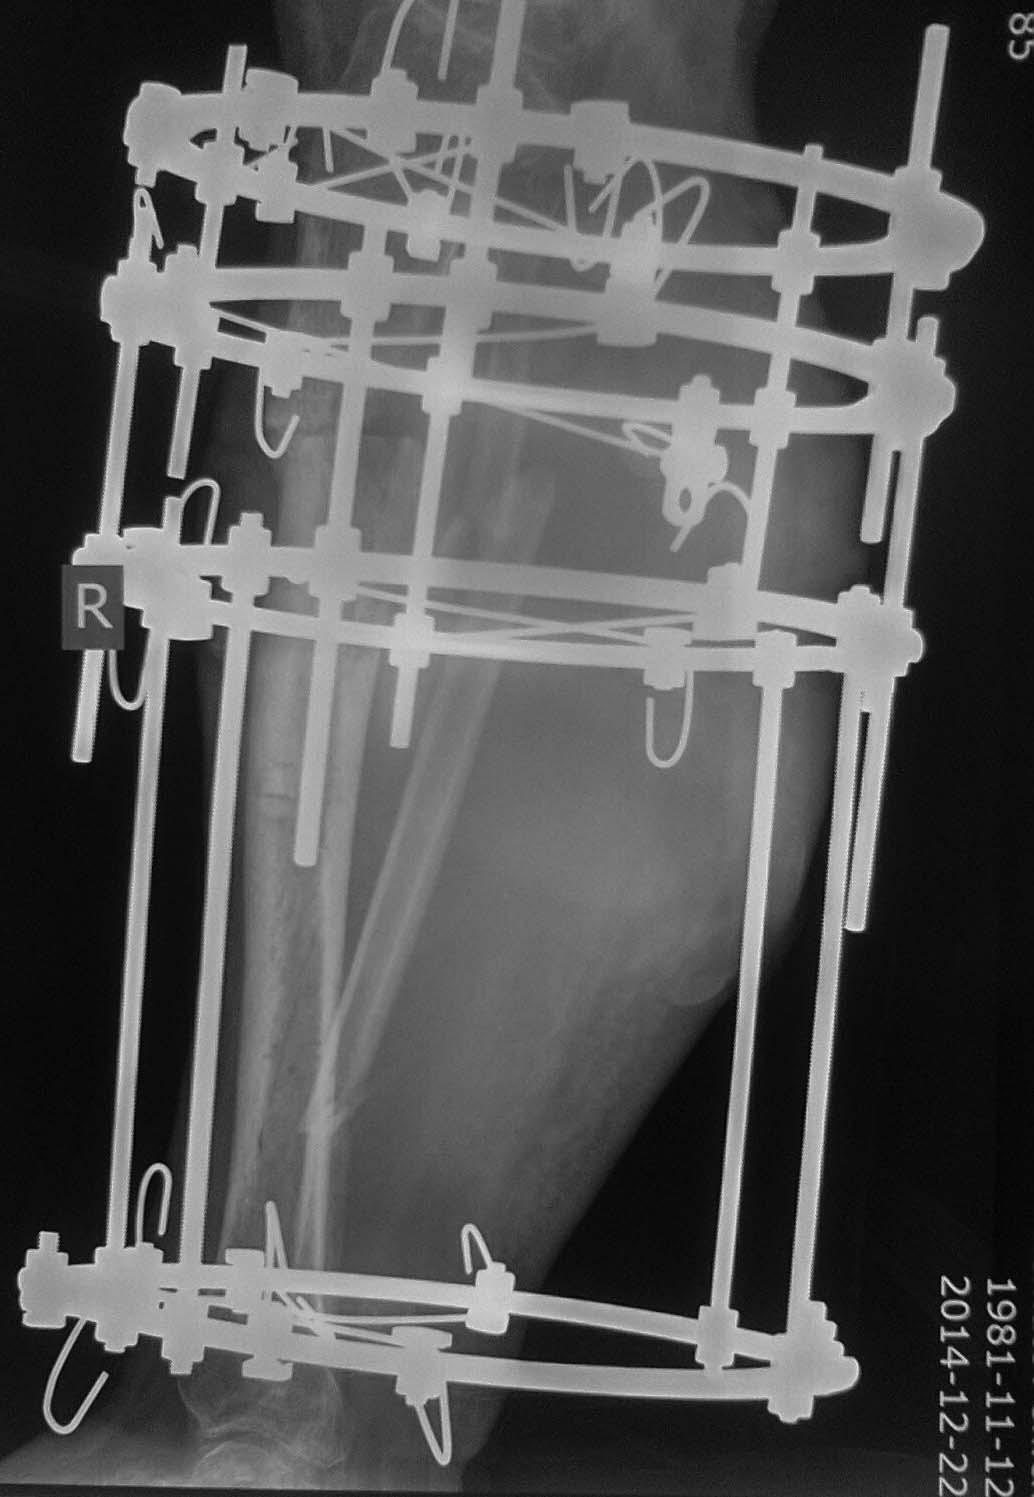

Неделю назад пришел снимать аппарат с рентгенограммами (фото 3,4). Ходит

с полной безболезненной нагрузкой на конечность, АВФ стабилен, раны от

опорных элементов спокойны, отек конечности умеренный, в проекции бывшей

гнойной раны- втянутый рубец (если необходим внешний вид конечности, то

смогу выложить на следующей неделе,наверное). Учитывая большой дефект

кости по задней поверхности кости, боимся, что при нагрузке без аппарата

произойдет перелом.

Вопрос: что делать?